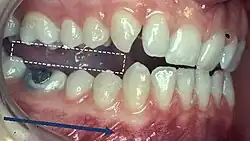

When describing the relationship between maxillary and mandibular incisors, the following categories make up Angle's incisal relationship classification:

- Class I: Mandibular incisors contact the maxillary incisors in the middle third or on the cingulum of the palatal surface

- Class II: Mandibular incisors contact the maxillary incisors on the palatal surface, in the gingival third or posterior to the cingulum. This class may be further subdivided into division I and division II:

- Class III: Mandibular incisors occlude with the maxillary incisors on the palatal surface, in the incisal third specifically or anterior to the cingulum

- In some cases the overjet is reversed (<0mm) and the mandibular incisors lie anterior to the maxillary incisors

- Class I: The mandibular first molar occludes mesially to the maxillary first molar, with the mesiobuccal cusp of maxillary first molar occluding in the buccal groove of mandibular first molar

- Class II: The mesiobuccal cusp of the maxillary first molar occludes anterior to the buccal groove of the mandibular first molar

- Class III: If the mesiobuccal cusp of the maxillary first molar occludes posterior to the buccal groove of the mandibular first molar[8]